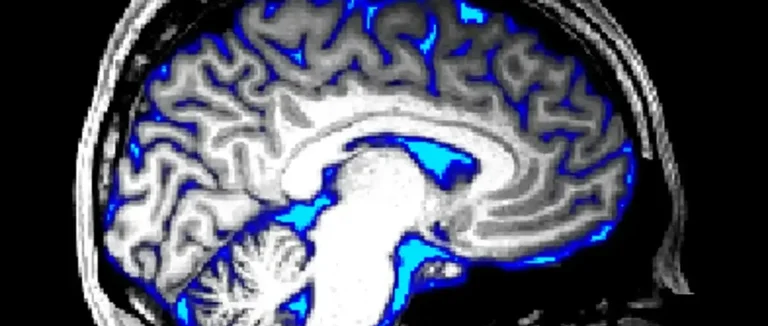

L'hydrocéphalie chez l'adulte est une condition complexe. Elle nécessite une compréhension approfondie pour un bon diagnostic et traitement. Cette condition affecte la circulation du liquide céphalo-rachidien (LCR) dans le cerveau, causant diverses complications.

L'hydrocéphalie se caractérise par une accumulation excessive de liquide céphalo-rachidien dans les ventricules cérébraux. Cela augmente la pression intracrânienne. Chez les adultes de 18 à 64 ans, environ 11 cas sur 100 000 sont diagnostiqués. La prévalence augmente chez les adultes plus âgés, atteignant jusqu'à 400 pour 100 000 chez les personnes de plus de 80 ans.

Le liquide céphalo-rachidien (LCR) protège et soutient le cerveau et la moelle épinière. Le corps produit environ 500 millilitres de LCR chaque jour. Ce liquide circule à travers les ventricules cérébraux et autour du cerveau et de la moelle épinière avant d'être réabsorbé dans la circulation sanguine.

La circulation normale du LCR est essentielle pour maintenir l'équilibre des fluides dans le système nerveux central. Toute perturbation dans cette circulation peut entraîner des problèmes, notamment l'hydrocéphalie.

● Le LCR est produit par les plexus choroïdes dans les ventricules latéraux et le troisième ventricule.

● Il circule à travers le système ventriculaire et dans l'espace sous-arachnoïdien.

● Le LCR est réabsorbé dans la circulation sanguine à travers les granulations arachnoïdiennes.

Comprendre la circulation normale du LCR est crucial pour diagnostiquer et traiter les anomalies, telles que l'hydrocéphalie.